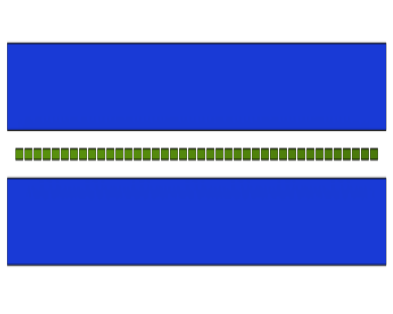

The J-PEM is a prototype intended to evaluate PET technology in the diagnosis of malign neoplasm in the breast and of ganglion loco-regional invasion. It is based on plastic scintillators and utilizes the same technology as the Jagiellonian Positron Emmision Tomograph, J-PET [31]. It is optimized for the detection of photons from electron-positron annihilation [32, 33]. Such photons, having an energy of 511 keV, interact with electrons in plastic scintillators predominantly via the Compton effect. J-PEM uses a dedicated instrument for breast cancer detection that is equipped with two parallel photon detectors in a configuration similar to mammography compressors. The detector system consists of two modules of plastic scintillators, with each module built from two layers of plastic scintillator and the wavelength shifters [34, 35] placed orthogonally between them, as shown in Fig. 6. Each scintillator bar is attached at both ends with Silicon Photomultipliers for the signal readout [32]. The combined use of plastic scintillators, which have superior timing properties, with the WLS strips can provide an affordable and precise scanner with significant improvement in spatial resolution and efficiency for the detection of breast cancer. Plastic scintillators are characterized by short light decay time which is in the order of 1.5 ns [32]. This enables one to achieve high time resolution. In the J-PET, solution for the position of the interaction point of photons is based on the measurement of the time of the signals arrival to the ends of the long scintillator strips. So far a resolution of about 10 mm was achieved [35]. In order to achieve high resolution, we propose to register scintillation light escaping the scintillator bar through a side wall using an array of WLS. It has been already proven that one can reach to position resolution of 5 mm for the coordinate along the scintillator bar.